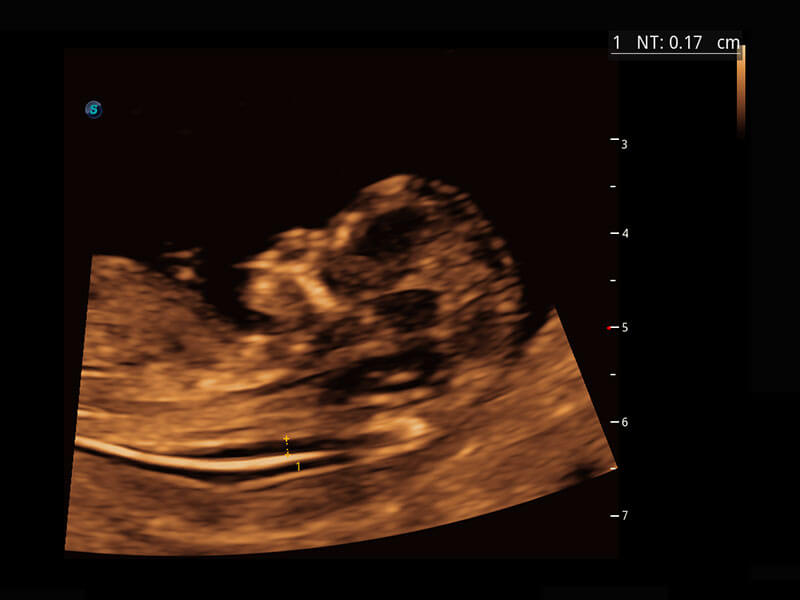

中晚孕筛查

P60提供简单易学易用的高端诊断工具,为您中晚孕筛查提供快速清晰的解剖信息。

1 OFD(HC): 87.03 mm

HC: 251.00 mm

GA: 27w 1d

HC/AC: 96.13 %

2 BPD: 70.56 mm

GA: 28 w 2d

S-Fetus(acq.)

& S-Fetus(meas.)

S-Fetus

S-Fetus能够助您在实时扫查过程中自动识别标准切面、自动测量并录入报告。一个按键,即可快速、高效地获取胎儿生理指标,简化您的产科检查操作。